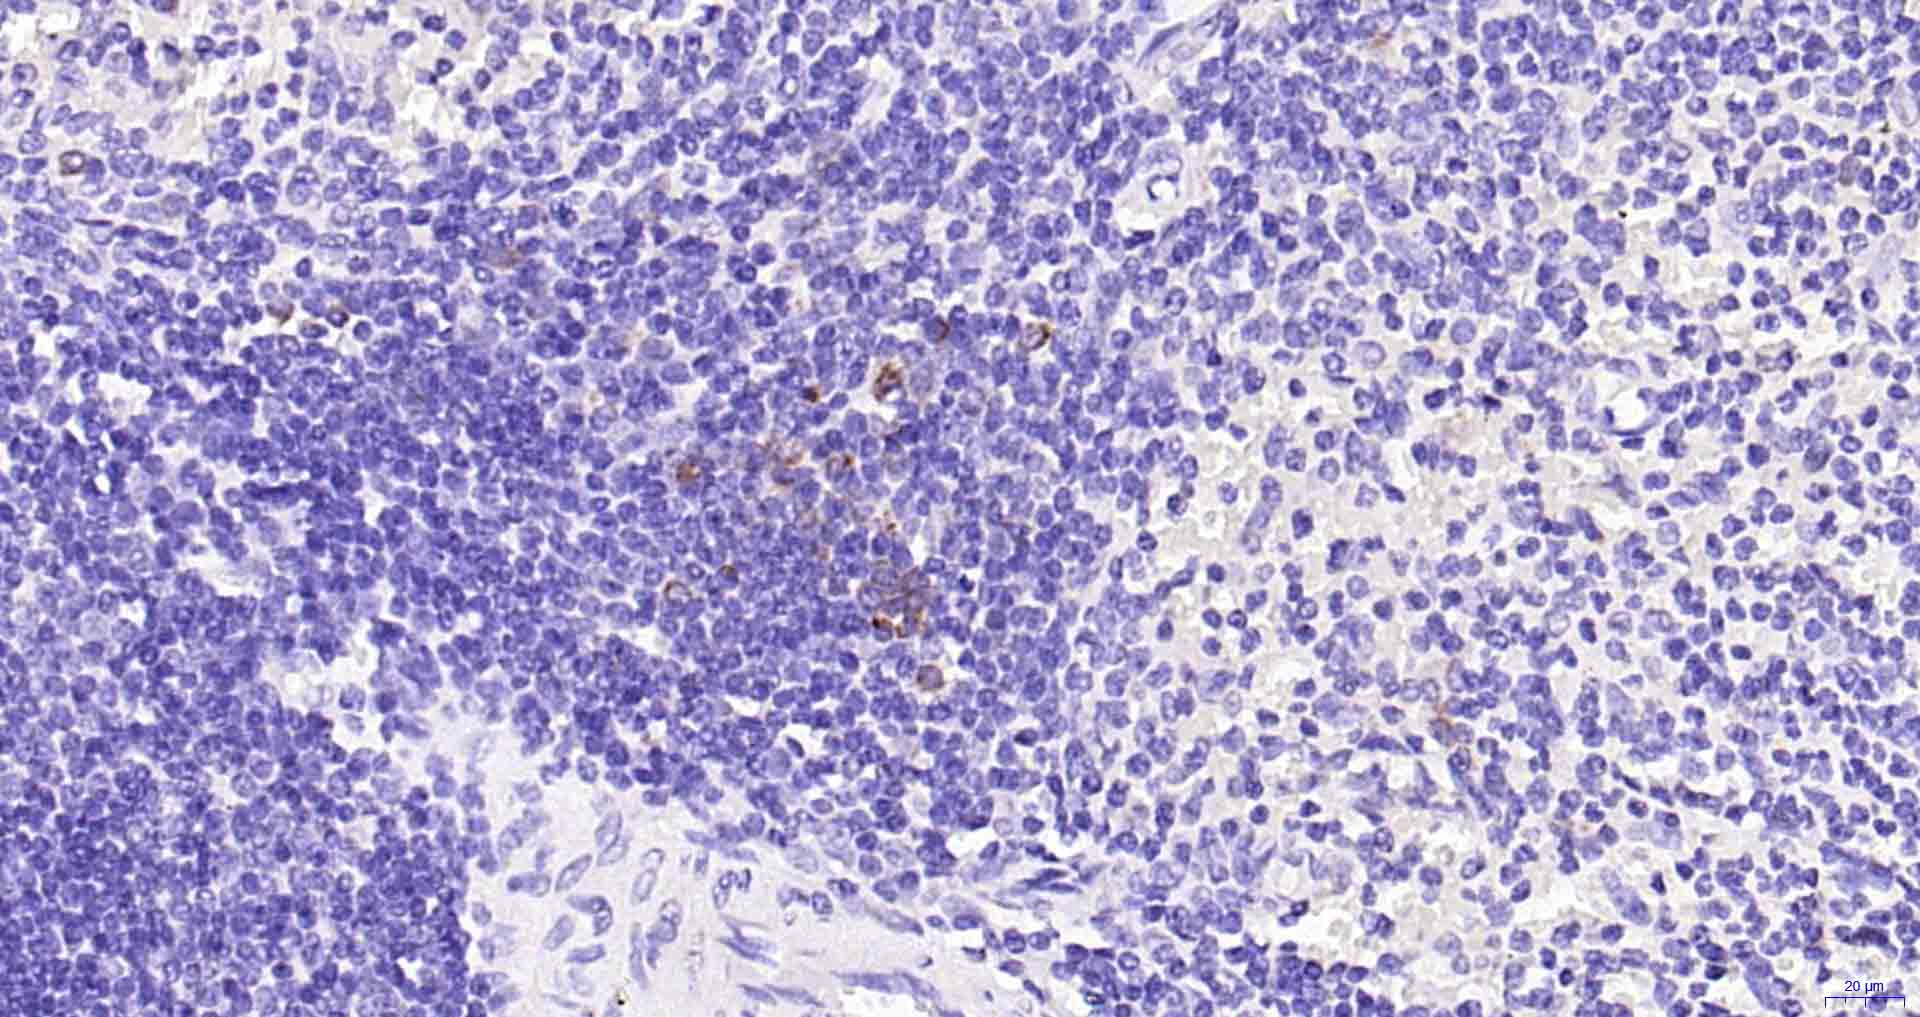

| IHC-P | Human | 1:50-200 | |